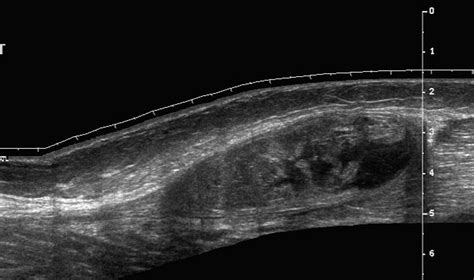

Calf muscle anatomy illustration

The calf is composed primarily of two major muscles: the gastrocnemius, which is the large, visible muscle that gives the calf its shape, and the soleus, which lies deeper underneath. Both of these muscles merge at the bottom to form the Achilles tendon, which attaches to the heel bone. When you push off the ground during walking, running, or jumping, these muscles work in harmony to plantarflex the foot (point the toes downward).

A tear in calf usually occurs when these muscles are stretched beyond their capacity during an eccentric contraction—when the muscle is lengthening while simultaneously trying to produce force. This frequently happens during sudden acceleration or a rapid change of direction.